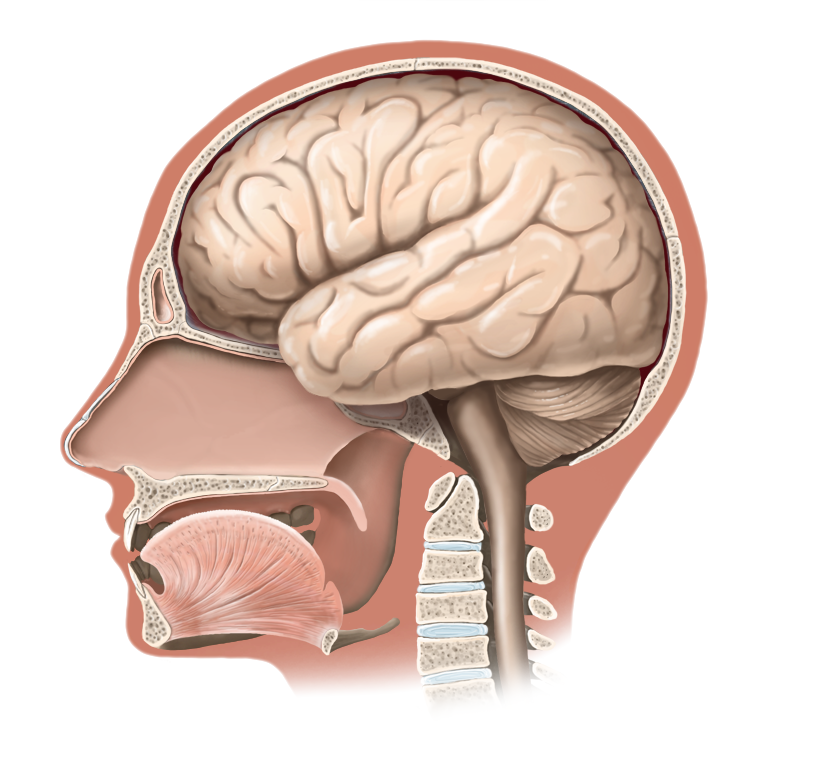

Medical Illustration

All images are works made for hire and are the exclusive property of the client. These are shown as sample purposes of my work only. For licensable work, please see my Illustration Services page.

Medical Illustrator for Precision Graphics, Lachina, and Human Kinetics Publishing (current)

Contract freelancer for many others, some examples of my work below.